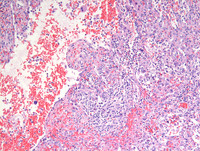

Figure 2: H&E images

As noted on medium power photomicrograph (Image on the left), vascular channels have irregular lumina with focal papillary projections. High power photomicrograph (Image on the right) reveals vascular channels that are lined by tall and plump, bland-looking cells, some of which are seen projecting and sloughing into the lumina. Cytologic atypia is not evident.